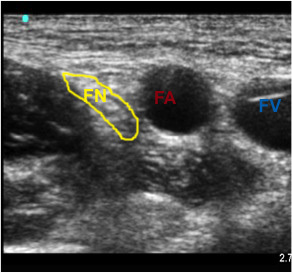

Published at 292 × 273 in Chapter 19: Regional Anesthesia